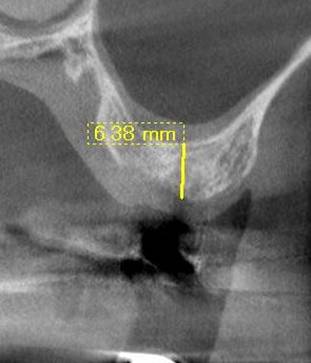

術後のCBCT

インプラントの重大な事故は下顎管から十分な距離をとれば防げます

抜歯部位にインプラントを追加しました。CBCT

インプラントとCT

術前。もっとも短いインプラントが8ミリですので、上顎洞に少し骨を押し上げる必要がありました。

インプラント埋入直後。骨を押し上げ、人工骨を入れています。

一年後、骨ができています。